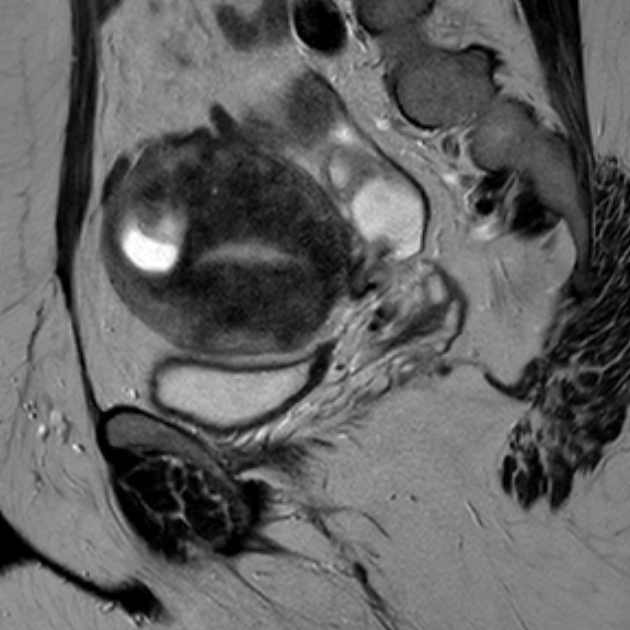

Bệnh cơ tuyến tử cung dạng nang (Cystic adenomyosis)